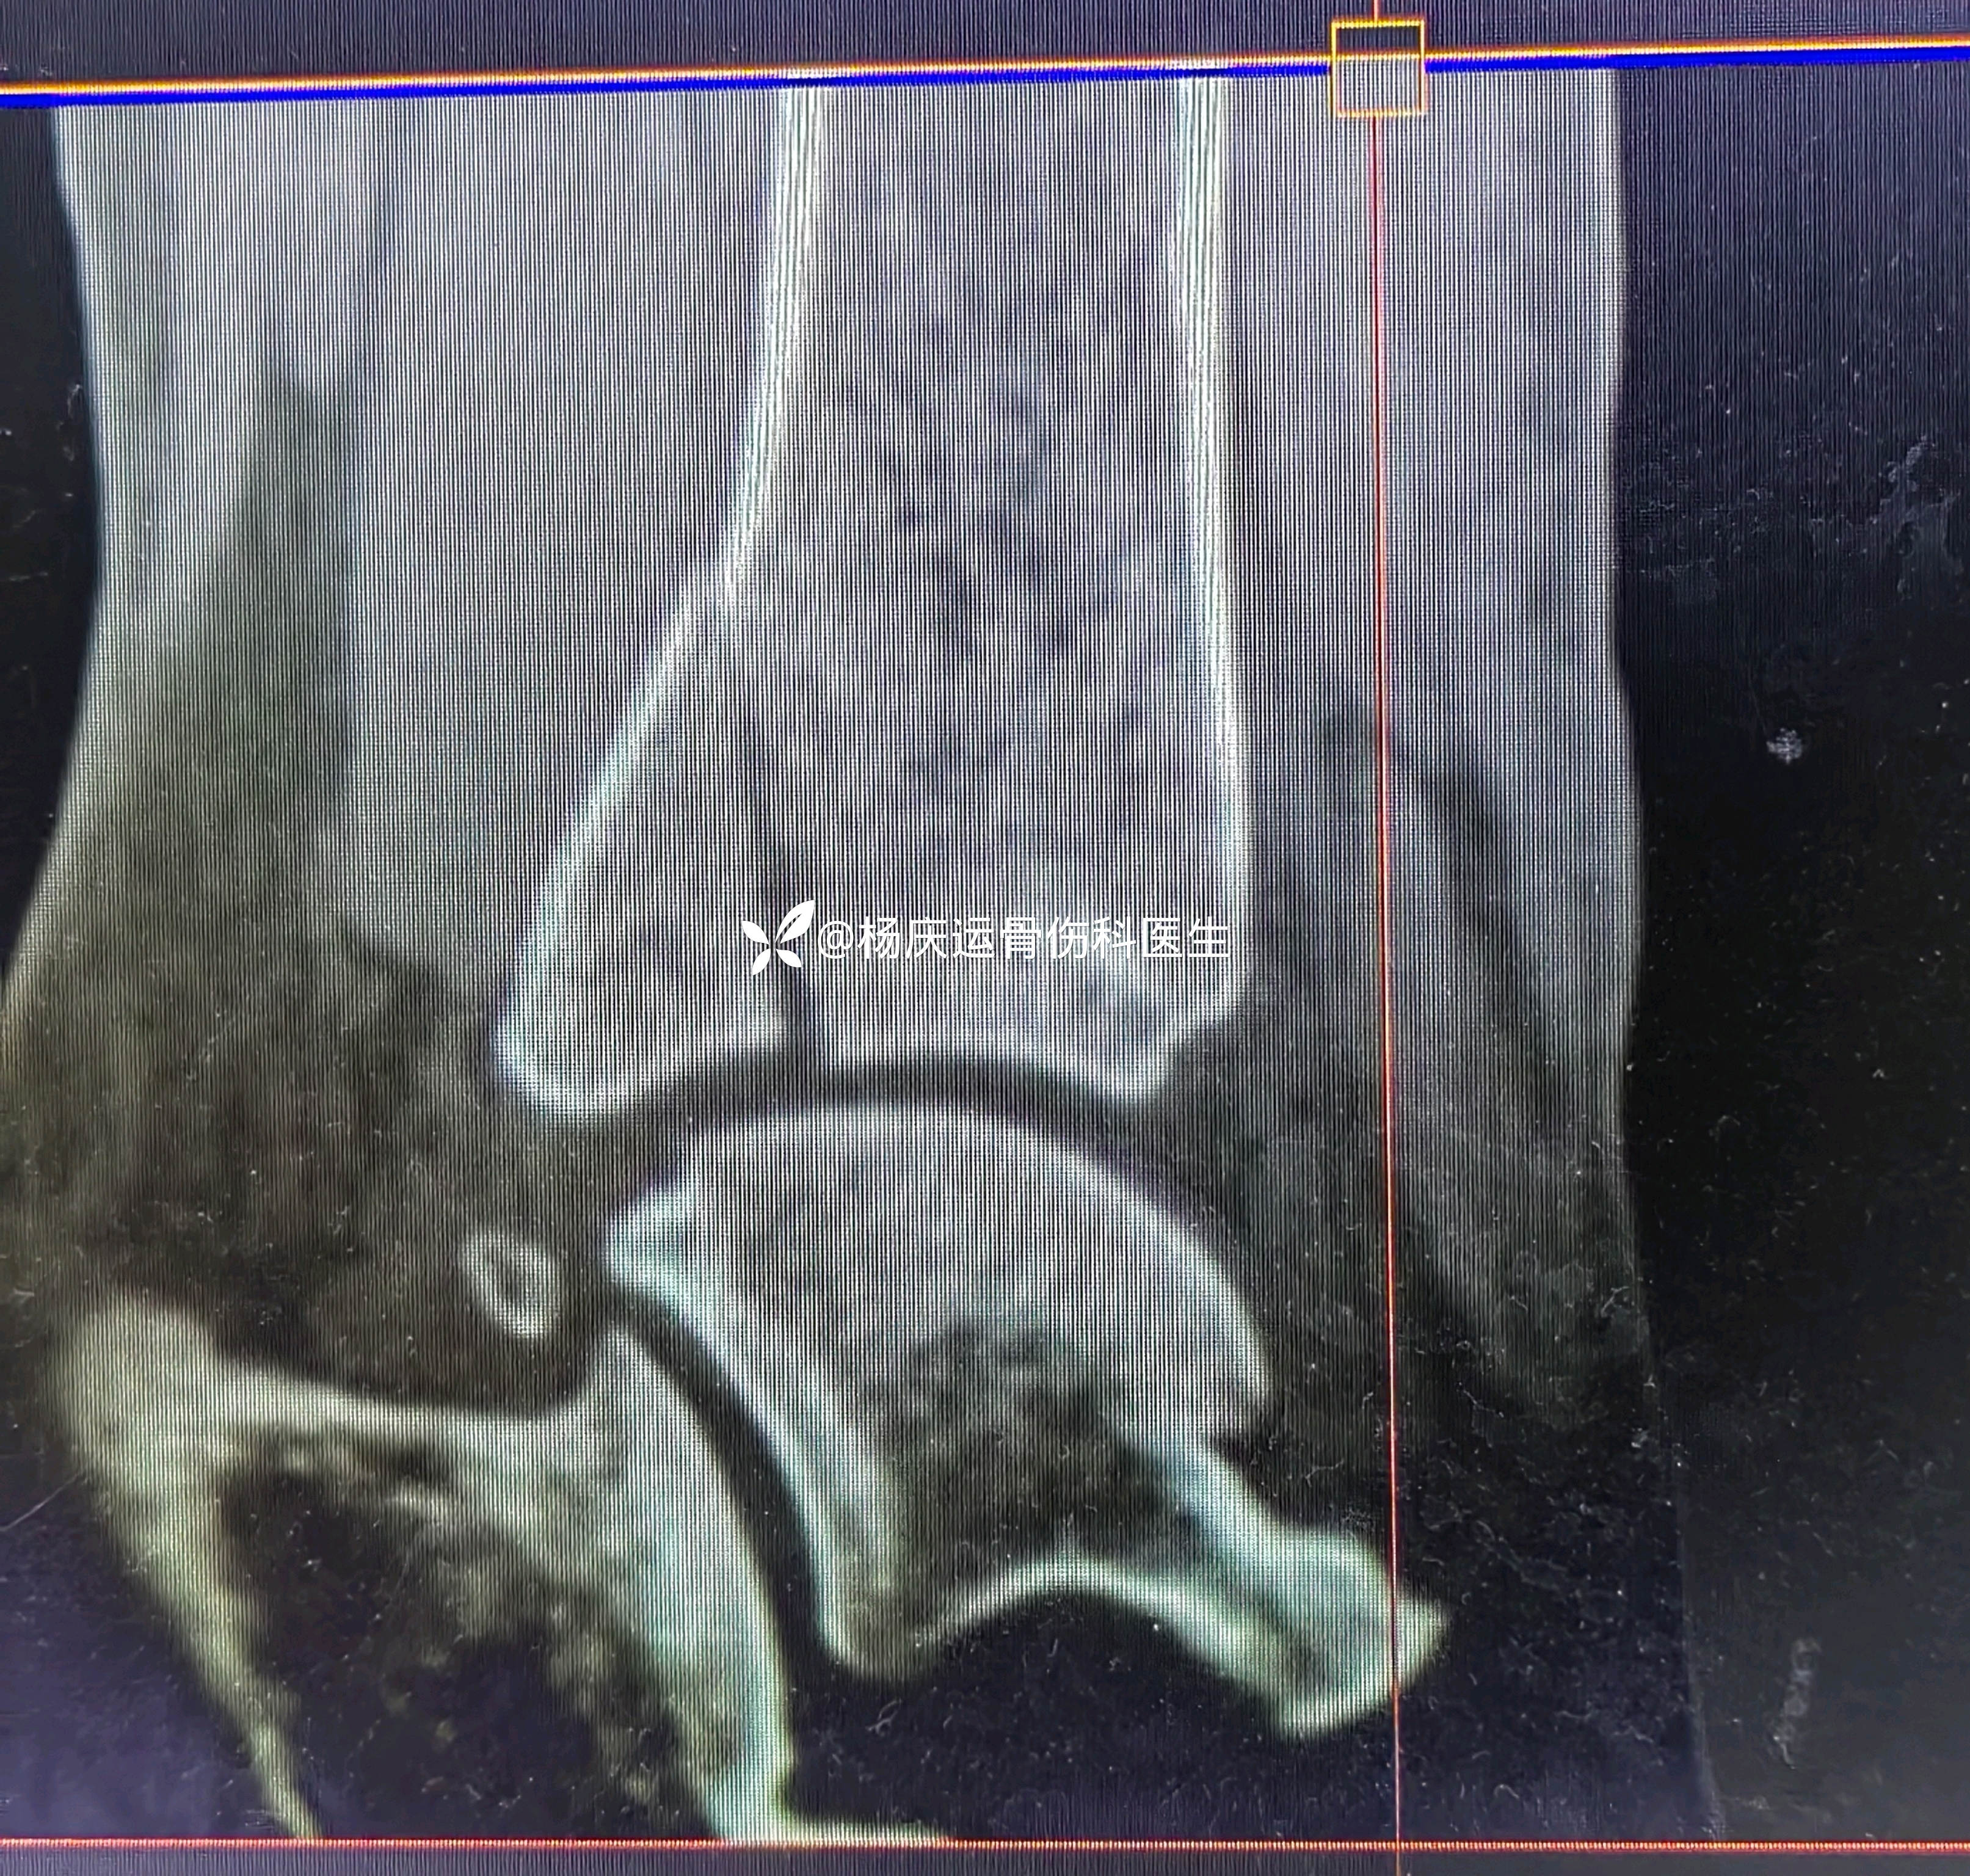

首诊三维CT

复位后